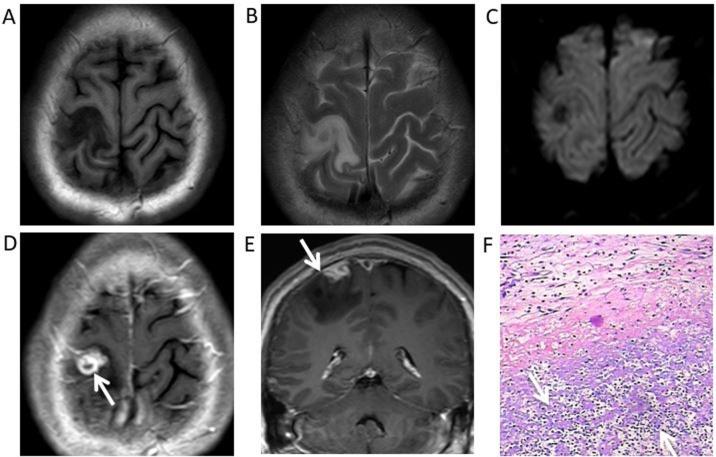

Cerebral syphilitic gumma is a rarely reported disease of the central nervous system. Magnetic resonance imaging (MRI) is an important diagnostic method for syphilitic gumma. The present study aimed to describe and characterize neuroimaging results from 6 patients with pathologically diagnosed cerebral syphilitic gumma. The 6 patients (age, 32-61 years) underwent brain CT and MRI, with 1 patient also undergoing whole-body 2-deoxy-2-(fluorine-18)fluoro-D-glucose-positron emission tomography/CT (18F-FDG PET/CT). Non-enhanced CT, conventional T1 weighted imaging (T1WI) and T2WI, diffusion weighted imaging (DWI) and gadolinium-enhanced T1WI images were acquired for all patients. The CT and MRI scans were retrospectively reviewed by two experienced radiologists for consensus on the location, number, size, T1WI, T2WI and DWI signal intensity characteristics, extent of vasogenic oedema, and enhancement patterns. In total, the 6 patients exhibited 10 lesions, nine of which were located in the cerebral hemisphere, primarily in the grey matter. The remaining lesion was located in the fourth ventricle, leading to mild-to-moderate hydrocephalus. The diameters of the identified 10 lesions ranged from 0.9-6.5 cm, with a mean diameter of 3.9 cm. The main feature observed in CT was low density and in MRI the features were T1WI and DWI hypointensity and T2WI hyperintensity. A single case exhibited syphilis gumma with massive haemorrhage. Ring-like or strip-like signs (n=5), accompanied by the dural tail sign (n=2) and homogeneous enhancement (n=1), were noted on T1WI with gadolinium. The 18F-FDG PET/CT performed in one patient of a cerebral syphilis gumma revealed low uptake and metabolism. The present study indicated that gadolinium-enhanced MRI combined with 18F-FDG PET/CT and laboratory examinations are helpful in distinguishing cerebral syphilitic gumma from brain tumors and infectious diseases, therefore avoiding unnecessary surgery.

脑梅毒瘤是一种中枢神经系统罕见病。磁共振成像(MRI)是诊断梅毒瘤的重要方法。本研究旨在描述和分析6例经病理诊断为脑梅毒瘤患者的神经影像学结果。这6例患者(年龄32 - 61岁)接受了脑部CT和MRI检查,其中1例还接受了全身2 - 脱氧 - 2 -(氟 - 18)氟 - D - 葡萄糖 - 正电子发射断层扫描/计算机断层扫描(18F - FDG PET/CT)。所有患者均采集了非增强CT、常规T1加权成像(T1WI)、T2WI、扩散加权成像(DWI)和钆增强T1WI图像。由两位经验丰富的放射科医生对CT和MRI扫描结果进行回顾性分析,就病变的位置、数量、大小、T1WI、T2WI和DWI信号强度特征、血管源性水肿范围及强化模式达成共识。6例患者共发现10个病灶,其中9个位于大脑半球,主要在灰质。其余1个病灶位于第四脑室,导致轻至中度脑积水。所发现的10个病灶直径范围为0.9 - 6.5 cm,平均直径为3.9 cm。CT主要表现为低密度,MRI表现为T1WI和DWI低信号、T2WI高信号。1例梅毒瘤伴有大量出血。钆增强T1WI可见5例呈环形或条状强化,2例伴有脑膜尾征,1例呈均匀强化。1例脑梅毒瘤患者的18F - FDG PET/CT显示摄取和代谢减低。本研究表明,钆增强MRI联合18F - FDG PET/CT及实验室检查有助于脑梅毒瘤与脑肿瘤和感染性疾病的鉴别,从而避免不必要的手术。